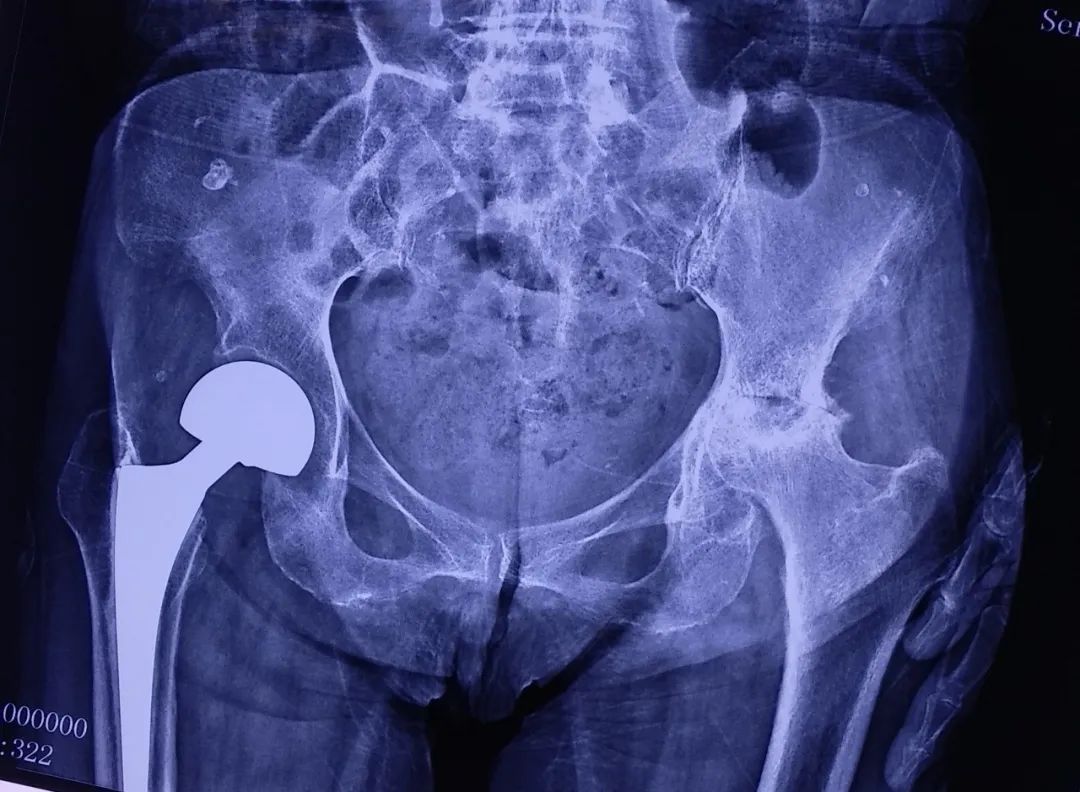

图:术后X线照片

图:麻醉科副主任、副主任医师王兆栋

手术由王副院长主刀,切口、保护好血管和神经,分离肌肉和筋膜,逐层显露髋臼及股骨头,垂直股骨颈截骨后,取出股骨头,磨好髋臼并安放髋臼假体及衬垫,扩髓后安放股骨假体柄,再连接好球头,最后将人工股骨头平稳推入髋臼后,手术顺利结束,整个操作手术过程历时50分钟,术中出血量不足150ml。